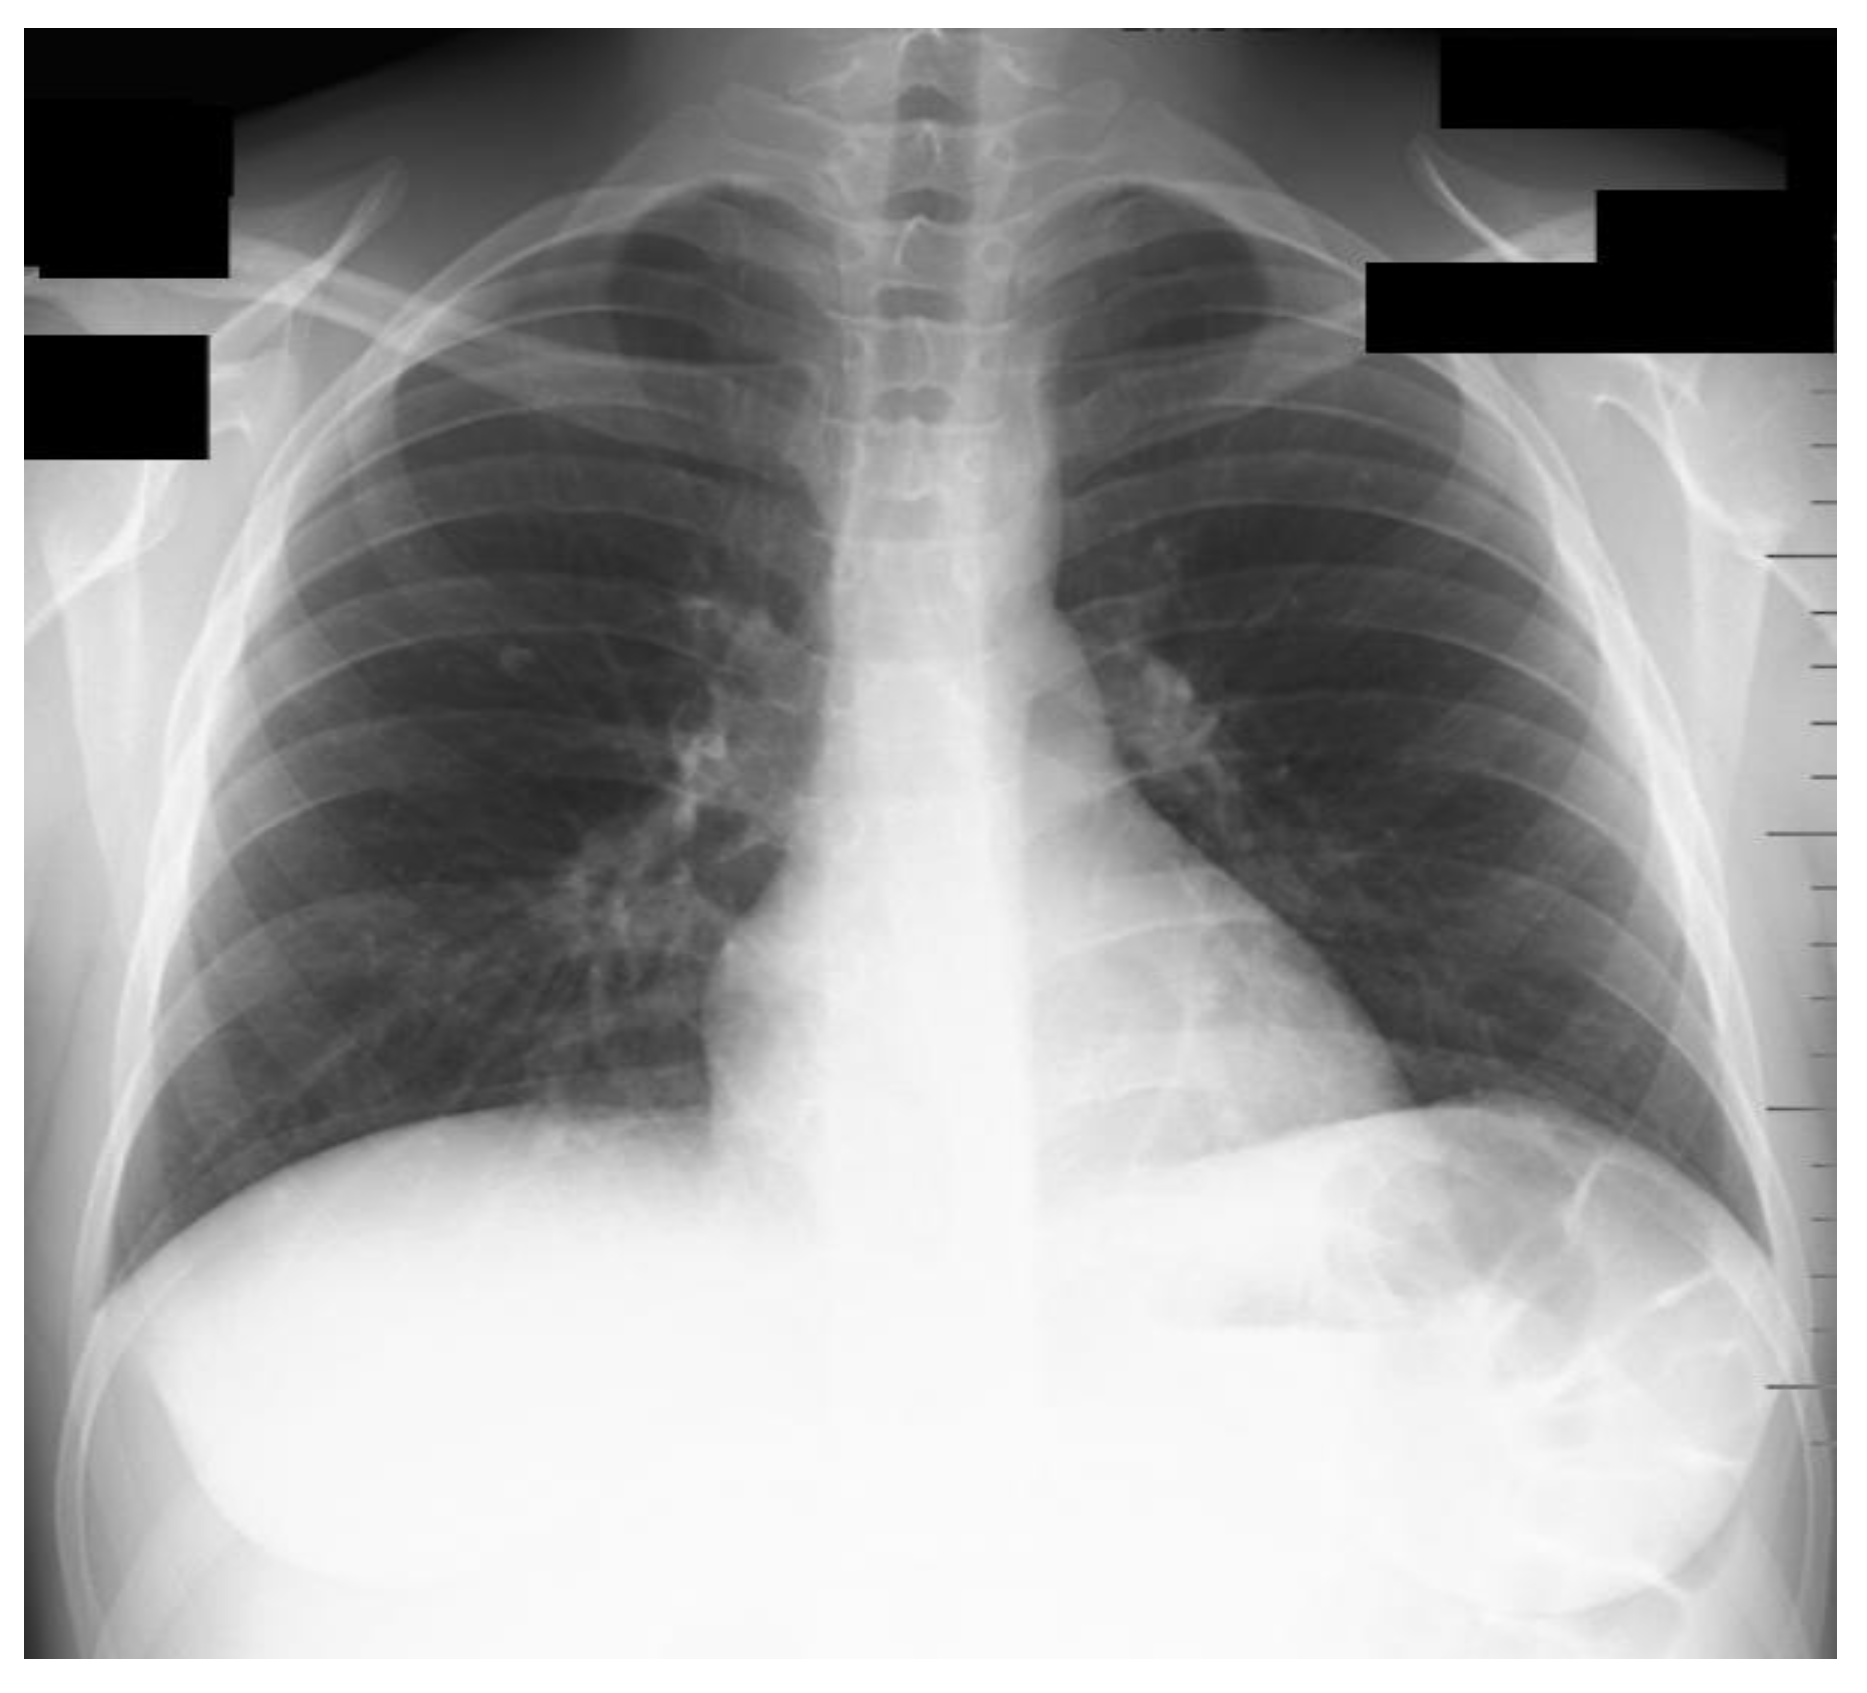

2. Case Presentation